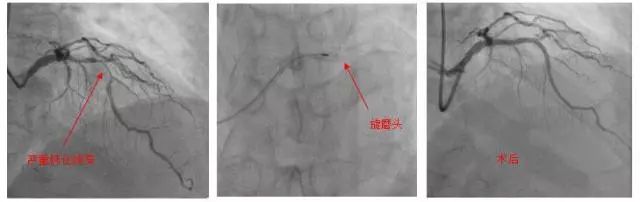

冠状动脉旋磨术处理严重钙化病变

近日,张大爷慕名来到北京大学国际医院心血管内科就诊时,杨胜利主任医师表示冠状动脉钙化斑块有些像石头一样坚硬,传统的球囊扩张常常难以奏效,强行扩张还可能导致血管撕裂或穿孔,只有尝试旋磨术来解决这一难题。

冠脉旋磨术,是使用一个头端布满微钻石的磨头,高速旋转下反复打磨钙化病变,以期达到钙化变薄、易于扩张的目的。因为技术要求高,国内仅少数中心可开展。

在与张大爷进行详细说明后,杨胜利主任医师和陈学智副主任医师为张大爷进行了手术,在反复的旋磨、扩张后,成功地在前降支病变处植入了两枚支架,开通了冠脉血流。